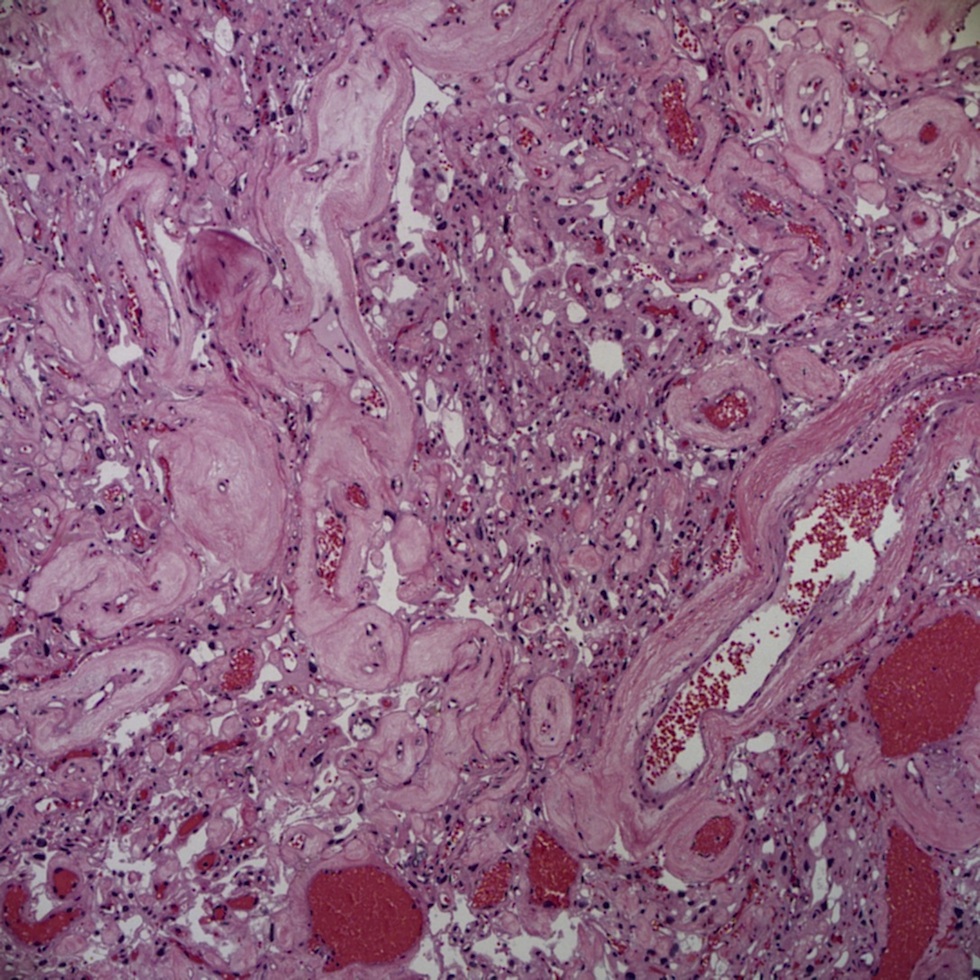

Микрофотографии гистологии глиобластомы головного мозга